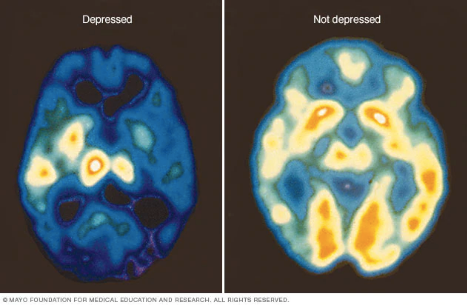

When you are depressed, you don’t run your thoughts — your thoughts run you. The hard part is not knowing what is the rational way to think, it’s actually thinking that way. Upon doing some research, I was surprised to find that the brain physically changes during depression (3): there is decreased activity in most part of the brain but an increase in Amygdala (emotion center); a cortisol (stress hormone) surge could result in shrinkage of the brain in the hippocampus (memory) and prefrontal cortex (decision making). What this means is a depressed brain tends to be more emotional and less rational. It comforts me to think I was not just being weak; being rational is difficult when your brain isn’t healthy.